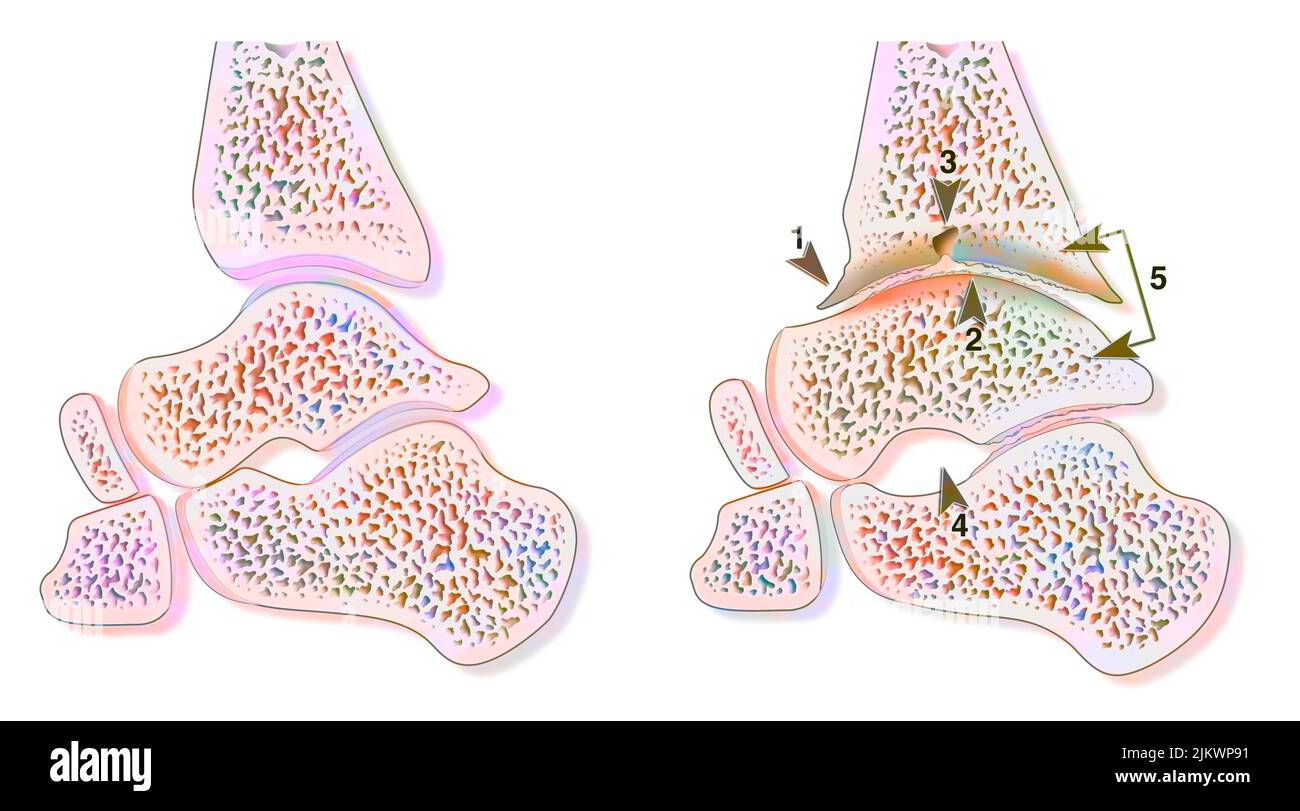

RF2WNN754–Illustration médicale des principales parties des os du pied en vue antérieure, avec annotations.

RF2R3WKY1–Illustration médicale des principales parties des os du pied en vue latérale, avec annotations.

RF2HJXCXK–Anatomie du pied.OS et fascia Plantar.Illustration vectorielle réaliste. Vue de dessous et vue latérale